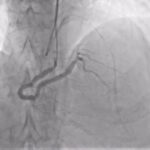

Η ορθόδρομη προσπέλαση αποτελεί την πλέον συχνά χρησιμοποιούμενη τεχνική στη διάνοιξη χρόνιας ολικής απόφραξης. Περιλαμβάνει την προσπέλαση της βλάβης από το εγγύς προς το περιφερικό άκρο της αρτηρίας, ακολουθώντας τη φυσιολογική φορά της αιματικής ροής.

Αν και είναι τεχνικά πιο απλή συγκριτικά με την οπισθόδρομη, ωστόσο η επιτυχία της περιορίζεται σε περιπτώσεις εκτεταμένης ασβέστωσης ή όταν η είσοδος της απόφραξης είναι ασαφής.

Από την άλλη, η ανάδρομη προσπέλαση εφαρμόζεται όταν η ορθόδρομη τεχνική αποτυγχάνει ή θεωρείται υψηλού κινδύνου. Αν και προσφέρει υψηλότερα ποσοστά επιτυχίας σε δύσκολες βλάβες, η ανάδρομη τεχνική απαιτεί μεγάλη εμπειρία και εγκυμονεί αυξημένο κίνδυνο επιπλοκών.